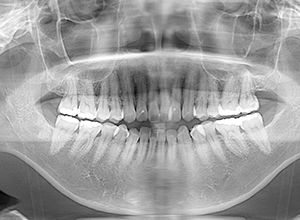

| セファロ所見 | Sellaから下顎頭までの距離は短く、骨体部は大きいが下顎枝の長さが短く、下顎角は開大しているためハイアングルを呈していた。中顔面部の高さは高いため下顎はクロックワイズローテーションをしており前後的にはII級の骨格形態を示していた。 |

| パノラマ所見 | 上下顎左右側8は欠損していた。 |